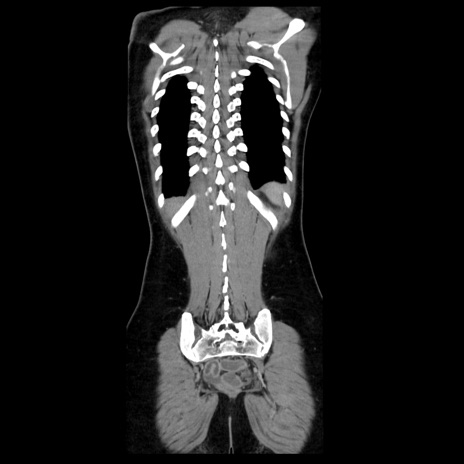

症例39(冠状断像)

【症例】40歳代女性

【主訴】上下腹部痛

【現病歴】2日目から下腹部痛あり。夜間は痛みで眠れなかった。昨日より上腹部痛と下痢が出現。臥位で痛みは軽快したため、休んでいた。本日になって臥位でも立位でも痛みが強くなってきたため救急要請。

【既往歴】子宮内膜症

【身体所見】部:平坦・軟、左上下腹部に圧痛あり、反跳痛あり。

【データ】WBC 21800、CRP 26.78

CT